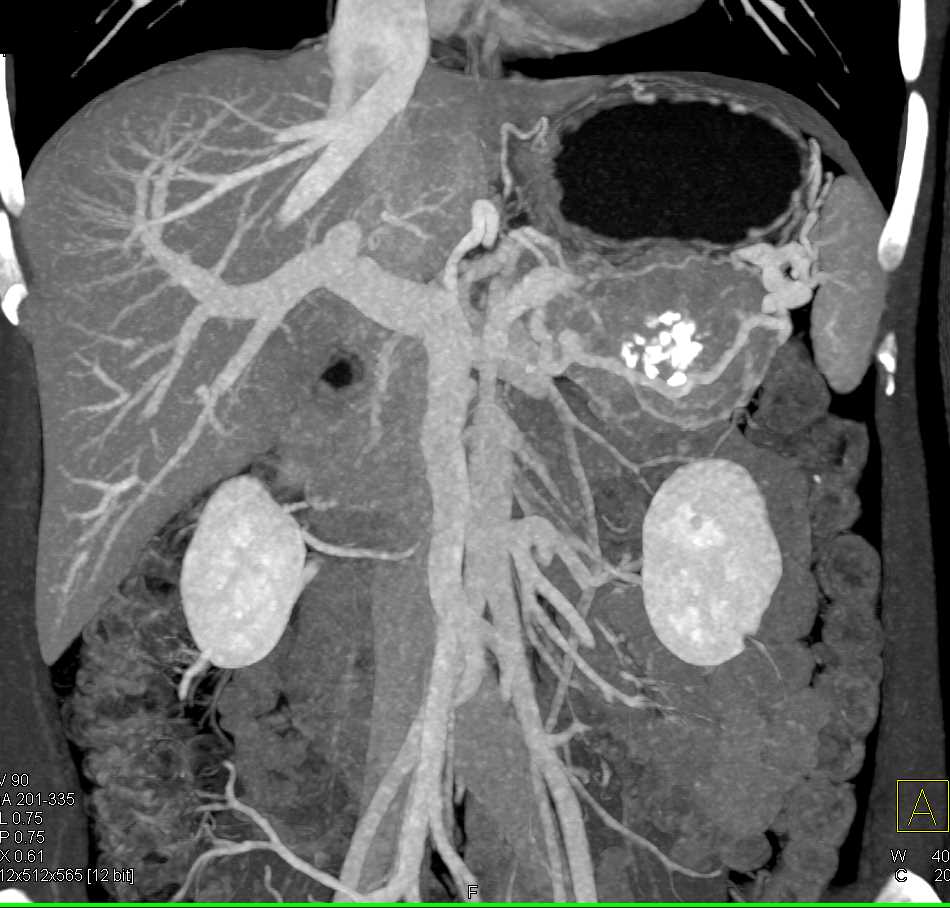

PNET Tail of the Pancreas